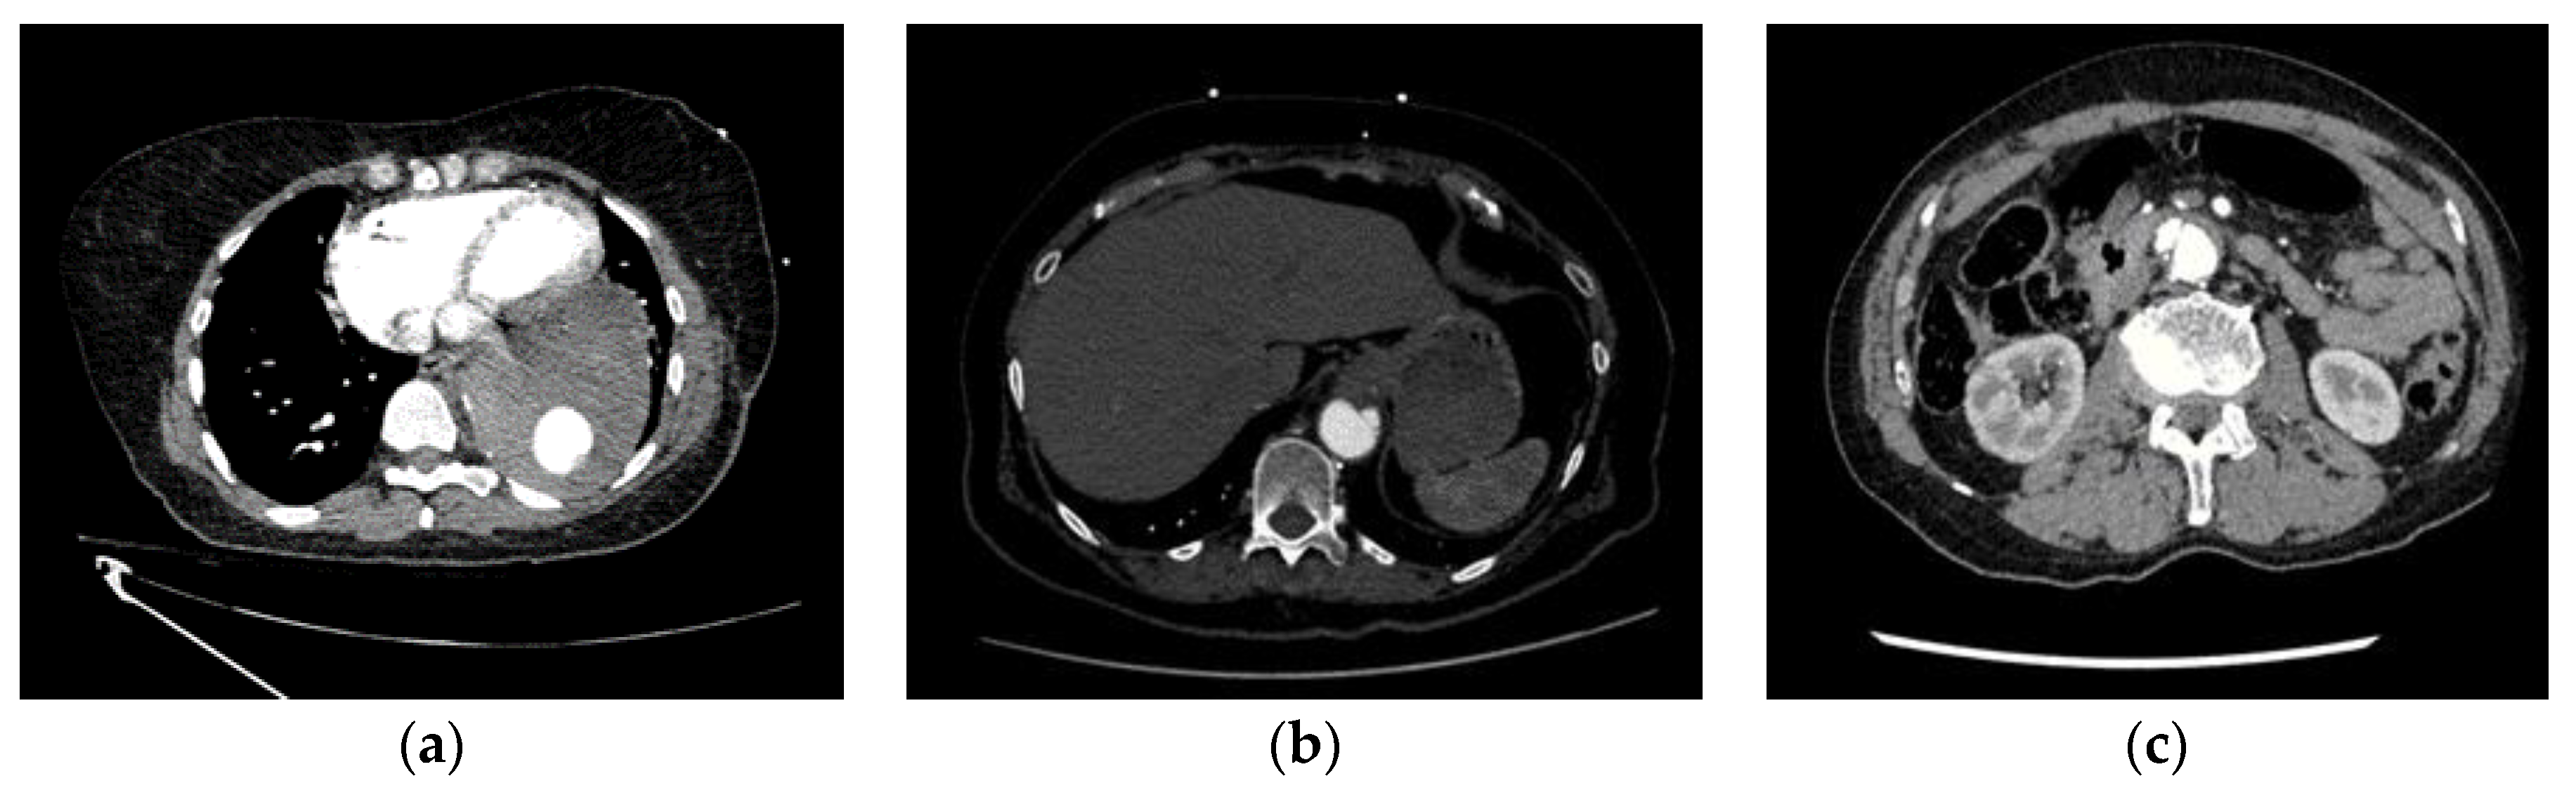

| Intramural hematoma (IMH) (4) | Inadequate contrast opacification (13) |

| Penetrating atherosclerotic Ulcer (PAU) (2) | Motion artefacts (10) |

| Acquisition artefacts (2) | Instances of pathology mimicking dissection (7) |

| Interference from stent grafts (2) |